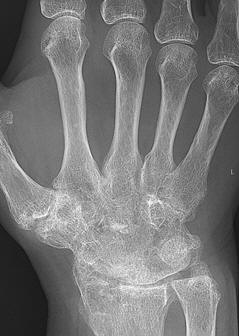

RA – Damaged fingers and wrist RA – Fused wrist bones

https://commons.wikimedia.org/wiki/File:Rheumatoid_arthritis_with_unaffected_carpal_bones_2009.jpg

| Description | English: X-ray of the wrist of a then 58 year old

woman with rheumatoid

arthritis, showing unaffected carpal bones. 8 years later,

she had developed ankylosing fusion of the bones - see File:Rheumatoid arthritis with carpal ankylosis

2017.jpg. |

| Date | 19 January 2009 |